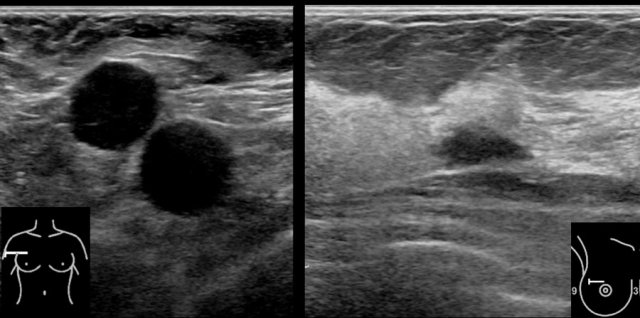

Here a typical example of multiple cysts in a woman who felt a lump in her breast.

Although there a many cysts, only the cyst in the center was palpable, because it was round with fluid under tension.

The other cysts were not palpable, because they just felt like the surrounding normal breast tissue.

It is very common to find more cysts in a woman who presents with a palpable cyst.

This woman had multiple small cysts in both breasts.

These cysts were not palpable.